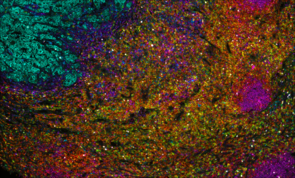

Multiplex immunofluorescence image showing tissue section with multicolor staining for different cell markers

Multiplex immunofluorescence image showing tumor tissue stained for Beta-Catenin, CD8α, E-Cadherin, FOXP3, Ki67, and PD-L1

Invasive ductal carcinoma Grade I stained with 6-plex mIF.

At Fortis, we use TSA on slides produced for the Akoya PhenoImager™ HT using Opal™ reagents to generate up to 6-plex images.